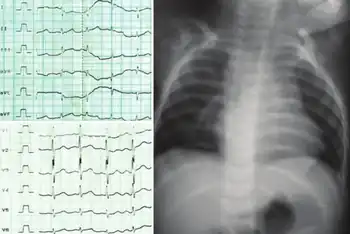

| Electrocardiogram left showed normal sinus rhythm with right ventricular hypertrophy with right axis deviation. Chest roentogram right showed levocardia, oligemia, cardiomegaly of right ventricle | |